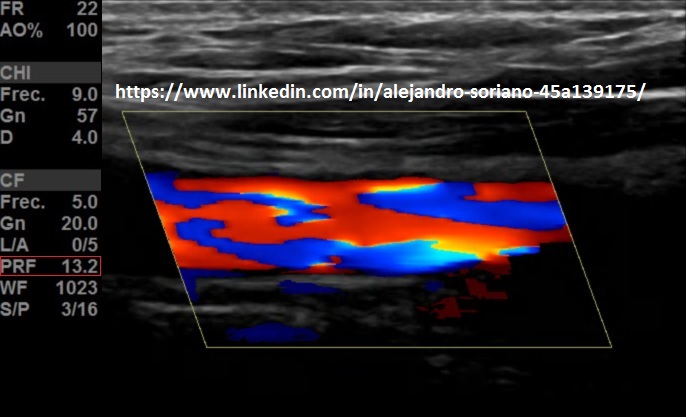

- Frecuencia de repetición de pulsos (PRF) o escala de velocidades: la modificaremos en función del flujo que estemos estudiando; para flujos de alta velocidad la aumentamos para evitar “aliasing”; para bajos flujos la disminuiremos para tener mayor sensibilidad.

- Podremos variar este valor en algún ajuste ecográfico situado en nuestra botonera o menú, que se denomine, generalmente, «escala»(Flecha amarilla).

Frequency of repetition of pulses or scale of speeds: we will modify it depending on the flow we are studying; for high-speed flows we increase it to avoid «aliasing»; for low flows we will decrease it to have greater sensitivity. We can vary this value in some ultrasound adjustment located in our keypad or menu, which is called, generally, «scale» (Yellow arrow).